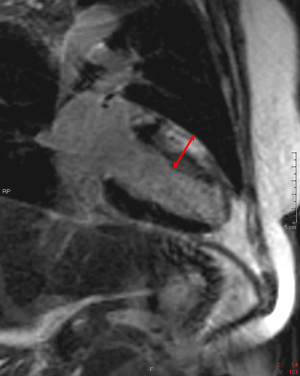

Answer: C. Aortic regurgitation and stenosis. There is both a stenotic jet which extends from the aortic valve into the ascending aorta during systole (arrow) as well as a smaller regurgitant jet extending from the aortic valve into the LV during diastole (arrowhead). Notice how there is minimal opening of the valve leaflets during systole, resulting in aortic stenosis. The right ventricle is not hypertrophied. With a ventricular septal defect, flow would be between the ventricles, which is not seen in this case. The severity of regurgitation or stenosis can be determined by the amount of signal void. Cardiac MRI has 98% sensitivity and 95% specificity for identification of aortic and mitral regurgitation. Higgins CB, Byrd BF, Stark D, et al. Diagnostic accuracy and estimation of the severity of valvular regurgitation from the signal void on cine magnetic resonance imaging. Am Heart J 1989; 118: 760-767.2) This inversion recovery sequence was taken 10 minutes after the administration of IV gadolinium. Which of the following entities does it show? ![]() Answer: B. DHE consistent with myocarditis. The image shows DHE (arrow) along the inferolateral wall of the left ventricle epicardium. The subendocardium is normal in this region. This finding is consistent with myocarditis as opposed to myocardial infarction in which DHE always involves at least the subendocardium. The structure within the left ventricular cavity is a normal papillary muscle seen in cross-section, not a thrombus or tumor. Laissy JP, Hyarfil F, Feldman LH, et al. Differentiating acute myocardial infarction from myocarditis: diagnostic value of early- and delayed- perfusion cardiac MR imaging. Radiology 2005; 237 (1):75-82.3) This horizontal long axis SSFP demonstrates which of the following entities? Answer: A. Apical septum wall motion abnormality. This cine shows a localized abnormality of the apical septum (arrow). The myocardium in this area does not thicken as much as the surrounding myocardium. When necessary, wall thickening can be quantified to assess region wall motion abnormalities. The remainder of the left ventricle functions normally, so global systolic of diastolic function is not present. Azhari H, Sideman S, Weiss JL, et al. Three-dimensional mapping of acute ischemic regions using MRI: wall thickening versus motion analysis. Am J Physiol 1990; 259:H1492-503.4) What are the primary physiologic consequences of the entity in the image shown below? ![]() Answer: C. Restricted diastolic filling and increase in venous pressures. The figures shown above are T1-weighted and T1-weighted with fat saturation images. The images show a pericardium that is thicker than 3 mm (arrows). This finding is consistent with constricted pericarditis in the appropriate clinical setting. Axel L. Assessment of pericardial disease by magnetic resonance and computed tomography. Journal of Magnetic Resonance Imaging 2004; 19(6):816-26.5) The cine below shows findings which are characteristic of which of the following? Answer: C. Arrhythmogenic right ventricular cardiomyopathy. The above cine shows a heart with marked RV dysfunction (arrow) out of proportion to the LV. The other entities listed would be expected to affect primarily the LV. Bluemke DA, Krupinski EA, Ovitt T, et al. MR Imaging of arrhythmogenic right ventricular cardiomyopathy: morphologic findings and interobserver reliability. Cardiology 2003; 99(3): 153-62.6) The gradient echo cine below shows what congenital abnormality? Answer: A. Atrial septal defect. There is a clear defect (arrow) in the superior aspect of the interatrial septum between the right and left atria. None of the other abnormalities are seen in this image. Wang ZJ, Reddy GP, Gotway MB, Yeh BM, Higgins CB. Cardiovascular shunts: MRI imaging evaluation. Radiographics 2003;23 Spec No:S181-94.7) This spin echo image shows what aortic abnormality? ![]() Answer: D. Aortic coarctation. This image shows an irregular narrowing at the aortic isthmus just distal to the left subclavian (arrow). MRI is especially useful in assessing the aorta after coarctation repair to assess for restenosis and the degree of collateralization utilizing VENC imaging. Kellenberger CJ, Yoo S, Valsangiacomo Buchel ER. Cardiovascular MR Imaginging in Neonates and Infants with Congenital Heart Disease. Radiographics 2007;27:5-18.8) Which of the following is shown in the IR image below acquired 10 minutes following infusion of gadolinium contrast agent? ![]() Answer: B. Subendocardial infarct. This image shows delayed hyperenhancement of the inferoseptal, inferolateral wall, and lateral LV wall. The DHE involves the subendocardium (arrow) which is suggestive of infarction, as opposed to the mid myocardial or epicardial location in myocarditis. The DHE does not involve the entire wall however, so it is a subendocardial as opposed to transmural infarct. A ventricular aneurysm would show a focal bulge of ventricular wall. Wu E, Judd RM, Vargas JD, Klocke FJ, Bonow RO, Kim RJ. Visualization of presence, location, and transmural extent of healed Q-wave and non-Q-wave myocardial infarction. Lancet 2001; 357 (9249): 21-8.9) The cine image below uses a technique specialized to determine what entity? Answer: C. Myocardial strain. This cine image uses a special modulation of magnetization to produce tag lines that move with the myocardium. The degree of deformation of the squares is used to calculate myocardial strain, which gives an accurate (sensitivity 92%, specificity 99%) quantitative assessment of myocardial function. A series of non-tagged short axis images can be used to measure ejection fraction, end-systolic volume and myocardial mass. Myocardial perfusion imaging uses gadolinium and adenosine. Gotte MJW, van Rossum AC, Twisk JWR, et al., Quantification of regional contractile function after infarction: strain analysis superior to wall thickening analysis in discriminating infarct from remote myocardium. J Am Coll Cardiol 2001; 37: 808-817.10) Which congenital cardiac anomaly is shown on the gradient echo cine below? Answer: A. Ebstein’s anomaly. In Ebstein's anomaly, the septal and posterior leaflets of the tricuspid valve (arrows) are displaced apically resulting in atrialization of the base of the right ventricle. The tricuspid annulus, however, is normally positioned between the right atrium and ventricle. The atrialized portion of the RV is thinned and prone to aneurysmal dilation. There is no connection between the two sides of the heart that would suggest a ASD or VSD. None of the findings of Tetralogy of Fallot are present. The pulmonic valve and aortic arch are not visualized in this slice. Choi YH, Park JH, Choe YH, et al. MR imaging of Ebstein’s anomaly of the triuspid valve. Am J Roentgenol 1994; 163:539-43.11) Below are pre and post gadolinium SSFP images. What abnormality do they show? ![]() Answer: D. Thrombus. The mass in the LV does not enhnance on post-contrast imaging, which is consistent with a thrombus. Thrombi form in regions of akinesis, typically due to myocardial infarctions. Microvascular obstruction is a process which involves the myocardium. Myxomas and metastatic disease typically have a heterogenous appearance and enhance. Papillary muscles enhance with myocardium. Friedrich MG. Magnetic resonance imaging in cardiomyopathies. J Cardiovasc Magn Reson 2000;2:67-82.12) Which of the following is seen on the gradient echo cine below? Answer: B. Pericardial effusion causing cardiac tamponade. There is a large amount of fluid in the pericardial sac (arrows). This fluid is physiologically significant because the contractile function of the heart is compromised and there is diastolic collapse of multiple chambers. The fluid is within the pericardium surrounding the heart, thus excluding pericardial cyst. The pericardium is not thickened, essentially excluding constrictive pericarditis. This diagnosis is usually made with echocardiography. Bilateral pleural effusions are also present. Wang ZJ, Reddy GP, Gotway MB, Yeh BM, Hetts SW, Higgins CB. CT and MR imaging of pericardial disease. Radiographics 2003; 23: S167-80.13) What abnormality is seen in this cine? ![]() Answer: C. Delayed hyperenhancement of hypertrophic cardiomyopathy. The DHE vertical long axis image demonstrates regional hypertrophy of the myocardium in the anterior wall (arrows) which is consistent with hypertrophic cardiomyopathy. There is also subepicardial and mid-myocardial delayed enhancement in the region of the hypertrophy which is due to fibrosis. Rickers C, Willke NM, Jero-Herlold M, et al. Utility of cardiac magnetic resonance imaging in the diagnosis of hypertrophic cardiomyopathy. Circulation 2005; 112(6):855-61.14) What abnormality is seen on the SSFP vertical long axis cine seen below? Answer: A. Myxoma. This cine shows a myxoma (arrow) within the left atrium that is partially prolapsing through the mitral valve. Myxomas are most often located in the left atrium, often pedunculated, and commonly attached to the interatrial septum. When large, they can obstruct the mitral valve and cause symptoms of mitral stenosis. Myxomas are well encapsulated unlike angiosarcomas which are a malignant tumor and are very invasive. A lipoma should have the same signal as subcutaneous fat, therefore it would be much brighter than this mass. This would be an unusual location for an intracardial thrombus, which typically form in areas of minimal motion. Sparrow PJ, Kurian JB, Jones TR, Sivananthan MU. MR Imaging of cardiac tumors. Radiographics 2005; 25(5): 1255-76.15) Below are perfusion images of basal, mid, and apical slices along with a delayed hyperenhancement image (bottom) aligned with the mid slice. The resting images are displayed on the top left with the Adenosine images displayed in the top right. What abnormality is seen in these images?